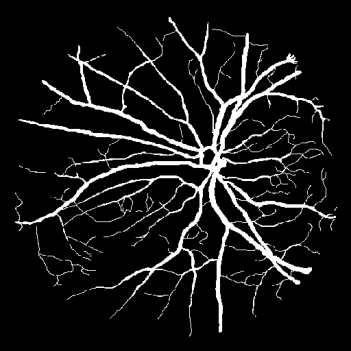

Vessel segmentation is an essential task in many clinical applications. Although supervised methods have achieved state-of-art performance, acquiring expert annotation is laborious and mostly limited for two-dimensional datasets with a small sample size. On the contrary, unsupervised methods rely on handcrafted features to detect tube-like structures such as vessels. However, those methods require complex pipelines involving several hyper-parameters and design choices rendering the procedure sensitive, dataset-specific, and not generalizable. We propose a self-supervised method with a limited number of hyper-parameters that is generalizable across modalities. Our method uses tube-like structure properties, such as connectivity, profile consistency, and bifurcation, to introduce inductive bias into a learning algorithm. To model those properties, we generate a vector field that we refer to as a flow. Our experiments on various public datasets in 2D and 3D show that our method performs better than unsupervised methods while learning useful transferable features from unlabeled data. Unlike generic self-supervised methods, the learned features learn vessel-relevant features that are transferable for supervised approaches, which is essential when the number of annotated data is limited.